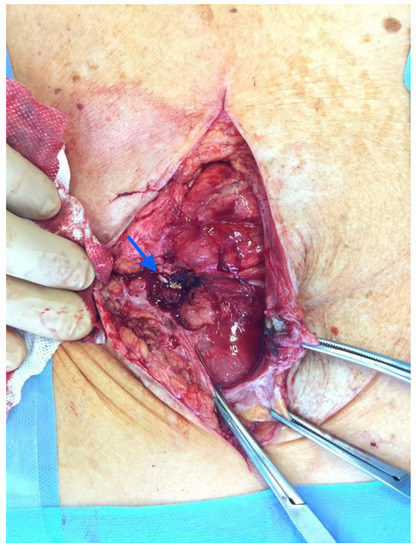

After the optimization of the patient’s nutritional status, a laparotomy, adhaeolysis, and jejunal resection were performed. A conglomerate consisting of the small intestine 80 cm from pl. duodenojejunalis was identified and a metal stent was palpated. The intestines 5 cm proximal to the blockage were found to be hypertrophic and considerably inflated (Figure 2 and Figure 3). The resection of 10 cm of the small bowel with the metal stent was performed and a jejunojejunal anastomosis was formed using a running 3-0 PDS suture (Figure 4).

Figure 2. Enterocutaneous fistula in situ (blue arrow).